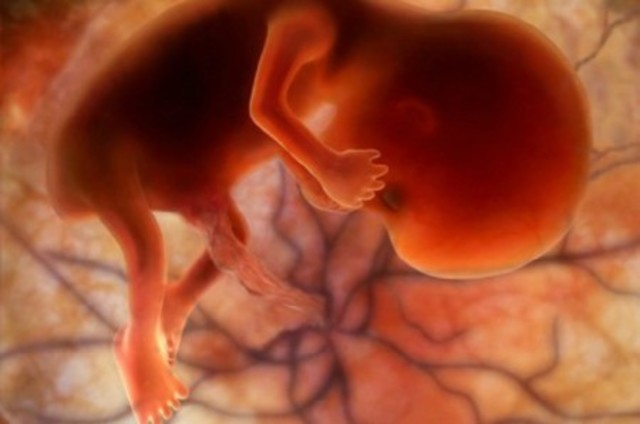

Termina el periodo de organogénesis, el crecimiento y maduración de todos los organos continuará en el periodo fetal

• Period: to

8va SDG

Externamente todas las estructuras están completas, la cabeza es mayor en relación con el tronco, las extremidades presentan sus 3 porciones , los dedos de manos y pies están separados aun que no tienen uñas el pédiculo de fijación se convierte en el cordón umbilical en el que todavía persiste la hernia fisiologíca la cual retornara a la cavidad abdominal en la decima semana , el embrión ya no presenta cola, el periodo embrionario termina en la 8va semana y empieza el periodo fetal.